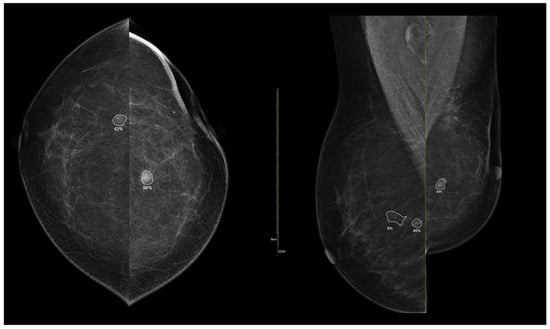

To illustrate the behavior of the iCAD ProFound AI® system across different biological phenotypes, Figure 9 and Figure 10 present representative examples corresponding to Group 1 (luminal) and Group 2 (HER2-positive/triple-negative) tumors. In both cases, the algorithm correctly identified the lesion with high confidence and localized regions corresponding to malignant radiomic traits. These findings should be interpreted in the context of case-level AI assessment rather than lesion-specific prediction.

Figure 10. Example of iCAD ProFound AI® output for a triple-negative breast carcinoma. The lesion detected on the low-energy image is automatically outlined by the AI system with an assigned malignancy probability. The outline shows the regions of highest AI attention, corresponding to oval shape and microlobulated, noncircumscribed margins.